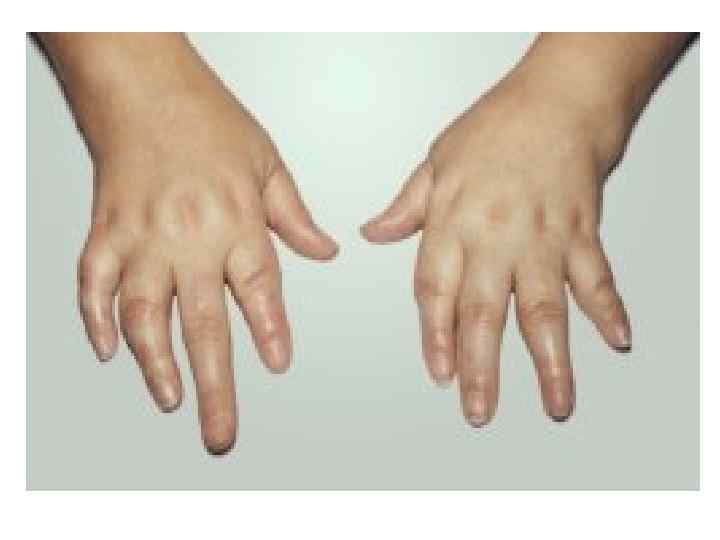

Клиническая картина • Жалобы: 1. Боль – наиболее ранний симптом! Выделяют два основных типа болей: Нейропатическая боль (акропарестезии). Постоянное жжение и покалывание, ощущение дискомфорта. Эта боль обычно затрагивает ступни и ладони. Кризы Фабри. Возникающие время от времени сильная, жгучая боль, возникающие в ступнях или ладонях и иногда распространяющиеся на другие части тела. Эта боль может быть весьма изнуряющей и продолжаться от нескольких минут до нескольких дней. 2. Нарушение потоотделения. 3. Быстрая утомляемость и непереносимость физических нагрузок. 4. Ангиокератомы - мелкие, красновато-фиолетовые безболезненные папулы на коже. С возрастом количество ангиокератом у больных увеличивается, также иногда увеличиваются размеры отдельных элементов сыпи (до 10 мм). Наиболее часто ангиокератомы располагаются в области губ, пальцев рук и ног, ано-генитальной области (при достижении половой зрелости).